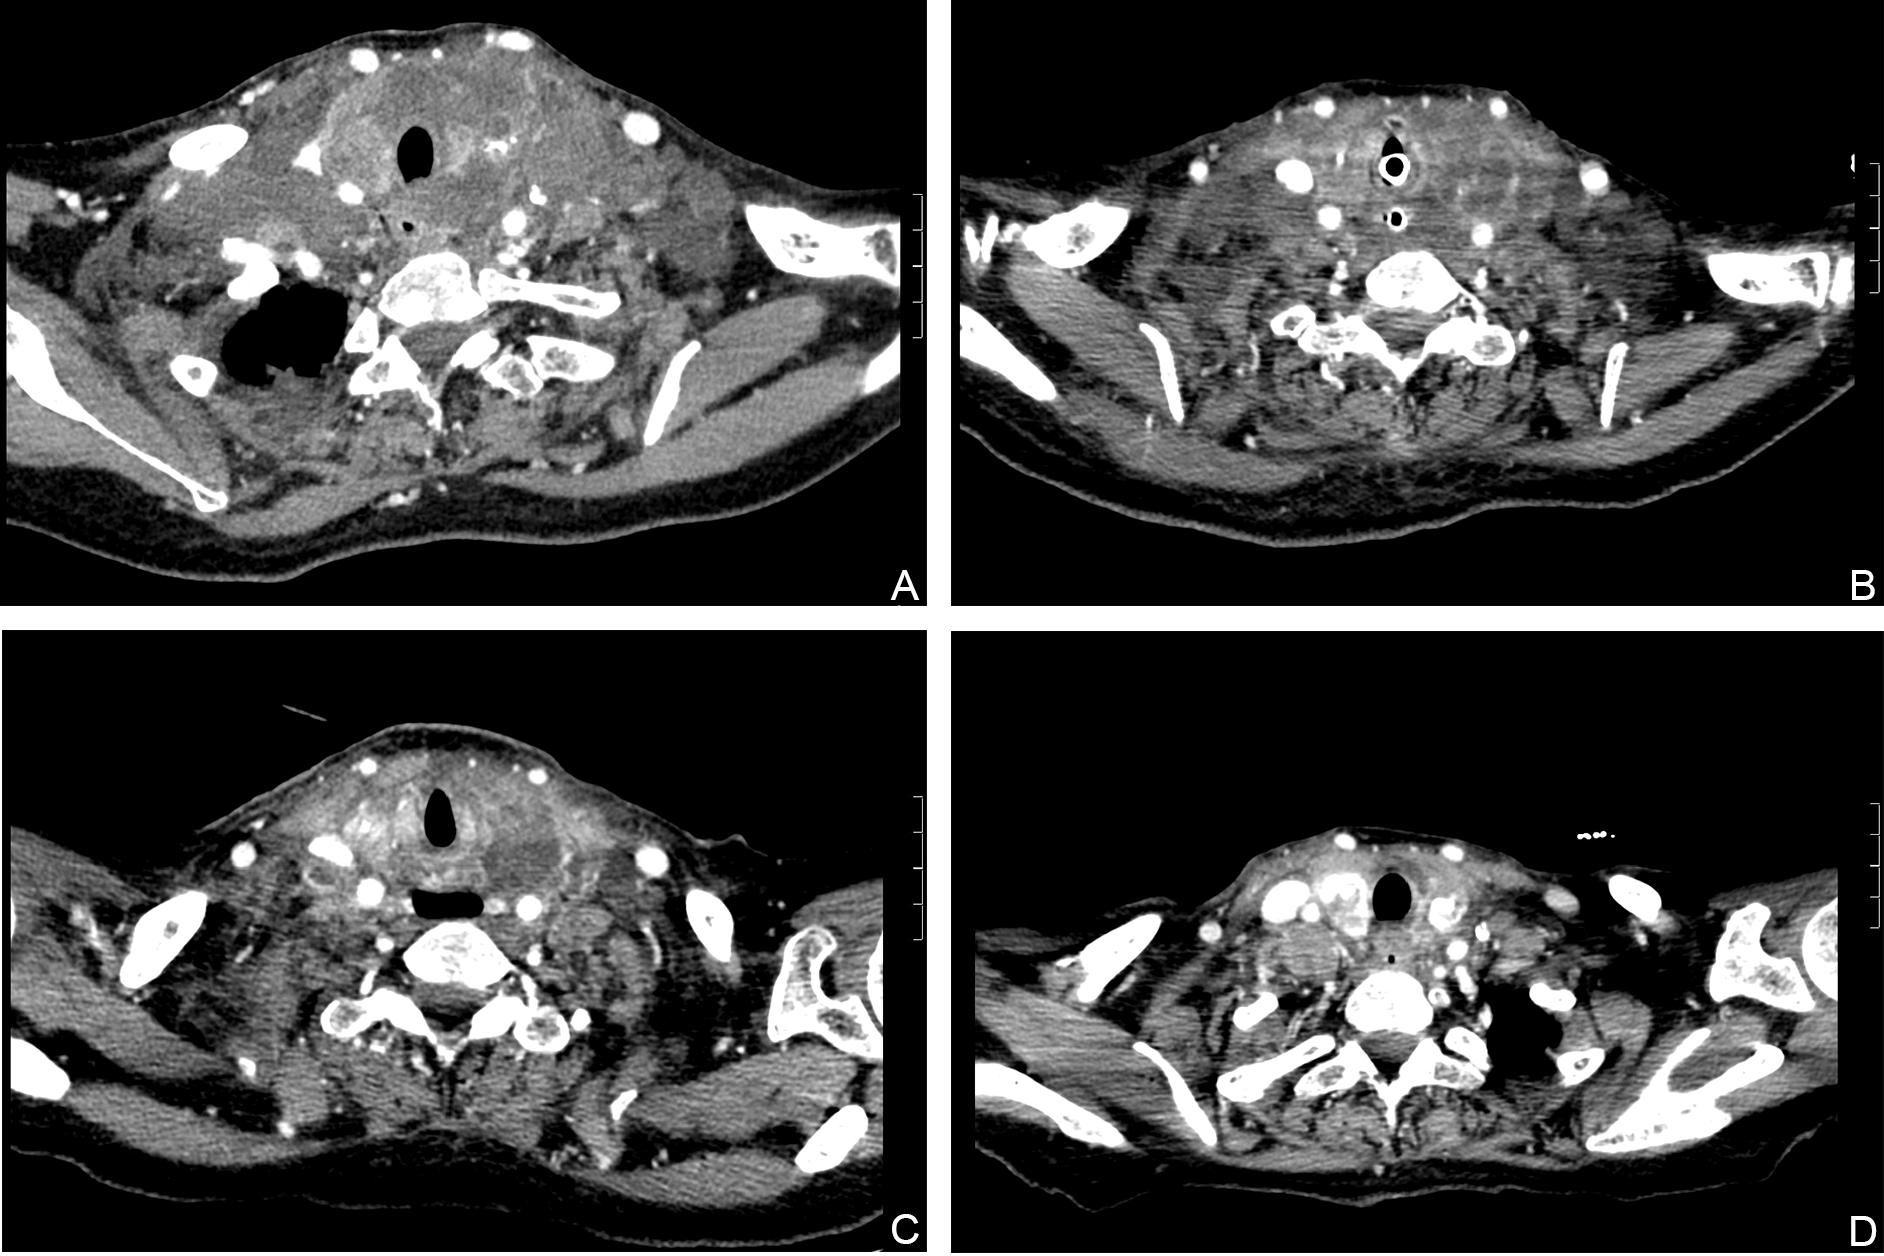

Physical examination showed that she had a hoarse voice, clear consciousness and diffuse swelling of the neck, and was unable to touch her trachea because of the trachea was compressed by a huge mass. The thyroid mass was hard, and its size could not be measured. The laboratory examination revealed the following: FT3 1.64 pmol/L (reference range, 3.60–7.50 pmol/L), FT4 9.53 pmol/L (reference range, 12.0–22.0 pmol/L), TSH 7.34 mU/L (reference range, 0.27–4.20 mU/L), thyroglobulin (hTg) < 0.04 µg/l (reference range, 3.5–77 µg/l), anti-thyroglobulin antibodies (TGAb) > 4000 IU/ml (reference range, 0–115IU/ml), and tumor marker/carcinoembryonic antigen (CEA) 0.64 ng/ml (reference range, 0–5 ng/ml). Ultrasound re-examination revealed that the thyroid gland contained giant nodules encircling the bilateral common carotid arteries. In addition, bilateral neck areas I-IV had multiple lymph node fusions, the left neck was approximately 12×10×16 mm, the right side was approximately 20×19×14 mm, and the corticomedullary demarcation was unclear. We showed on computed tomography (CT) that the thyroid gland was unclear and there were lymph node metastases in the neck and upper mediastinum (Figure 1). The patient had a personal history of 20 years of hypothyroidism and had taken 50 µg levothyroxine (Euthyrox) for a long time. There was no history of neck surgery, neck radiotherapy, parathyroid disease, or hereditary disease.

Figure 2

Computed tomography (CT) images showing that the size of the lesions had decreased. (A) Before treatment with dabrafenib and trametinib. (B) Dabrafenib and trametinib for 5 days. (C) Dabrafenib and trametinib for 19days. (D) Dabrafenib and trametinib for 50days.